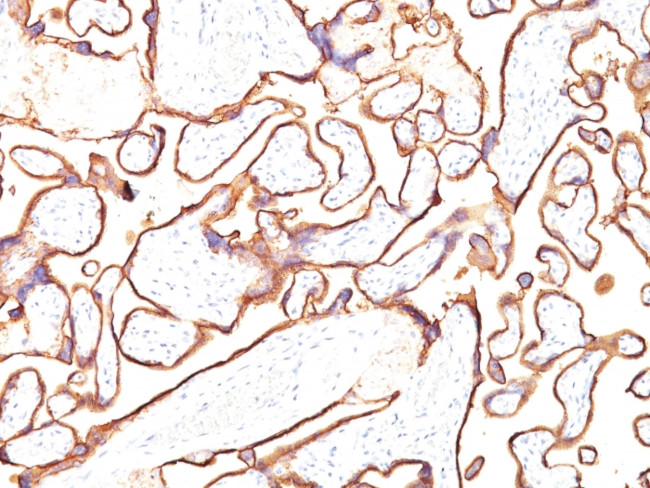

Alkaline Phosphatase (Placental)/PLAP (Germ Cell Tumor Marker) Antibody in Immunohistochemistry (Paraffin) (IHC (P))

Formalin-fixed, paraffin-embedded human Placenta stained with PLAP Monoclonal Antibody (PL8-F6). {{ $ctrl.currentElement.advancedVerification.fullName }} 验证信息 View more